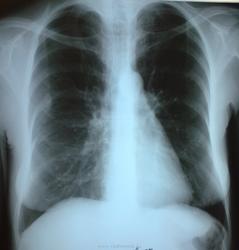

1969г., женщина, жалоб нет, профисследование,курит, в стационаре по поводу заболевания ЖКТ( не уточнено какое - "первым делом- самолеты", т.е. рентген ОГК).

Придираться или нет?

Конечно же придираться, если были убраны косы, если чист архив

Кос нет, архив пытаюсь. Дело в том, что коллега пишет R + и все. М.б. РЫ +?

Найдёте в архиве такое же, согласитесь с коллегой, а если нет, придётся производить "раскопки". Я бы вот так сходу, не зная, что было раньше, не рискнула бы сразу лепить R+. Ну хоть поговорить с пациенткой можно, анамнез порасспросить?

Так и поговорил: не болела, а я в сомнении "лепить Р+ "smiley.

Извините, а справа - консолидированный перелом заднего отрезка 7 р?

Думаю, нет. Ребро с лопаткой скрестились.

Ожидаемое. Рентгенолог см. рентгенорамму, видит что-то невнятное на верхушке, фиброз не фиброз. На дообследование вызвать? А, это будет R+!

По злобности моего характера, невзирая на возражения и "посмотрим в динамике", уговорил лаборанткуsmiley( не мой кабинет!) сделать томограммы.